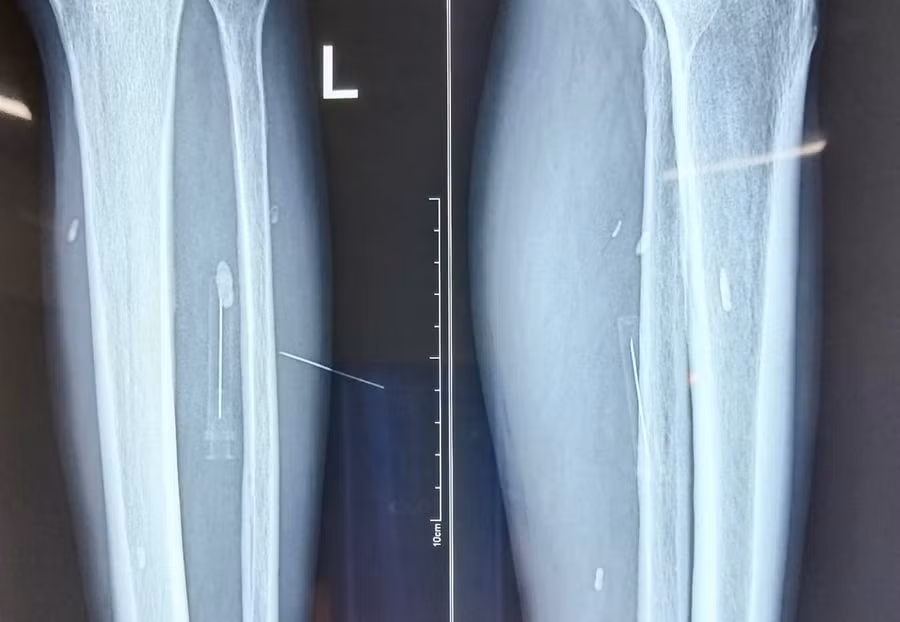

Mảnh đạn pháo nằm trong chân trái của bệnh nhân Minh. Ảnh: BV CA tỉnh Tuyên Quang

Sau khi nhập viện và được được thăm khám tỉ mỉ, đối chiếu và kiểm tra cận lâm sàng bệnh nhân đã được các bác sĩ phẫu thuật thành công gắp dị vật là mảnh đạn pháo dài 3cm.